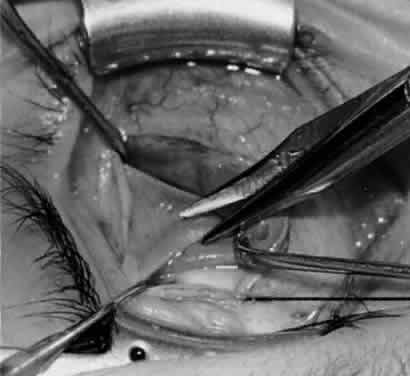

and extirpation, and anterior transposition.10 MYOTOMY An inferior oblique myotomy usually is performed between the nerve to the inferior oblique muscle and the insertion of the muscle. After the muscle is crushed with one or two hemostats, transverse surgical sectioning of the muscle is performed. Suture ligatures or cautery may be used for hemostasis. If the inferior oblique muscle is isolated properly, this procedure is not complicated and is performed rapidly. The severed ends of the inferior oblique muscle tend to reunite, however, and the preoperative state may be resumed within several months.2,10 MYECTOMY An inferior oblique myectomy includes removal of a section of the muscle to reduce the tendency of the myotomized ends to reunite. Two hemostats are used, as with the myotomy, except that a space of 5 mm or more is maintained between the hemostats, so that the segment of muscle between the hemostats can be removed. Cautery, ligature, or both are used for hemostasis. This procedure offers the same advantages as the myectomy but the cut ends still tend to reunite.10 Parks2,11 performed a controlled prospective study comparing the various methods of weakening the inferior oblique muscle. The study included 638 consecutive patients who had a minimum follow-up of 2 years. Parks performed 19 myectomies at the origin of the inferior oblique, 86 myectomies at the insertion, 89 disinsertions, and 444 recessions of inferior oblique muscles. The overaction of the inferior oblique muscle returned in 79% of the 19 eyes that underwent a myectomy at the origin. Because the recurrence rate is high and the procedure is difficult to perform, this procedure is no longer performed. Myectomy at the insertion produced a 37% return on overaction, also causing that procedure to be abandoned by Parks. Many authors, however, still prefer this procedure and advocate its use. Dyer1 reported a 91% success rate in reducing the hypertropia to 10 diopters or less, and Davis and coworkers12 reported a 93% success rate. DISINSERTION Disinsertion occurs at the scleral attachment of the inferior oblique muscle. Assuming proper exposure of the inferior oblique, this procedure is performed rapidly. The reattachment rate of the inferior oblique tendon is not predictable, however. It has a tendency to attach at or near the original insertion site or to the inferior border of the lateral rectus muscle.10 Parks2,11 found a 53% rate of return of overaction, worse than that for the myectomy procedure at the insertion end. Jones and associates,13 however, reported a success rate of 88% with inferior oblique disinsertion. RECESSION In comparing the various weakening procedures, Parks2,11 concluded that the recession procedure was superior (Figs. 1–20). The major advantage of the recession is that it allows the weakening procedure to be titrated according to the severity of the overaction. For 1+ overaction, the inferior oblique muscle is recessed 6 mm; for 2+ overaction, 10 mm; and for 3+ overaction, 14 mm, which is the maximum recession. A double-armed 6-0 synthetic suture, such as polyglactin (Vicryl [J-562]*) with a half-circle spatula needle (S-28*), is placed within the insertion of the inferior oblique with a locked bite at the anterior and posterior border (see Fig. 11). With an Aebli scissor, the muscle is sectioned from the globe (see Fig. 12) and recessed 6 mm by placing the anterior suture 4 mm lateral to the lateral insertion of the inferior rectus muscle and the posterior suture 3 mm more laterally. The 10-mm recession (see Figs. 15, 17, 18, 20) requires placement of the anterior suture 2 mm temporal and 3 mm posterior to the temporal insertion of the inferior rectus muscle, with the posterior suture placed 3 mm more posteriorly. The 14-mm recession (see Figs. 14, 16, 19, 20) requires placement of the anterior and posterior sutures parallel to the inferior-temporal vortex vein, which usually is found 8 mm posterior to the temporal insertion of the inferior rectus muscle.

Ethicon, Somerville, NJ. Ethicon, Somerville, NJ. Because the inferior oblique muscle inserts near the macula, there may be concern about penetration of the macula with a preplaced suture, which can cause macula hemorrhage, visual impairment, or visual loss. An alternative is to place a hemostat near the insertion of the inferior oblique muscle and then section the muscle from the globe with the Aebli scissor. The 6-0 Vicryl suture can be placed within the muscle, which is grasped by the hemostat and a locked bite placed at the anterior and posterior borders of the muscle, before the muscle is reattached to the sclera at the intended position. The technique of removing the inferior oblique muscle with the hemostat is part of the denervation and extirpation procedure. The disadvantage of the recession procedure is the difficulty involved in performing the procedure within a small operative field with limited visibility, compared with the myectomy or disinsertion. With proper illumination, however, such as the surgeon wearing the operating headlight and exposure with the Desmarres or Conway lid retractor, the inferior oblique insertion readily can be seen for placement of sutures and separation of the inferior oblique from the sclera. Parks2,11 found that 15% of patients had a return of overaction with the recession procedure, compared with 79% with myectomy at the origin, 53% with disinsertion, and 37% with myectomy at the insertion. Short-term follow-up is not helpful with oblique muscle surgery because inferior oblique overaction can return gradually over 2 years.10 Therefore, long-term follow-up is necessary for proper evaluation of success. In a more recent report, Wilson and Parks14 found a 25% recurrence rate of inferior oblique overaction after surgery, with an average follow-up of 3 years. Only 6% of patients required repeat inferior oblique surgery, however. DENERVATION Gonzalez15 first described denervation of the inferior oblique muscle as a weakening procedure but also reported the return of overaction within the first postoperative year.16,17 The nerve to the inferior oblique is attached tightly to the posterior belly of the inferior oblique muscle, lateral to the inferior rectus muscle border. At this site is a fusiform enlargement of the belly. After the nerve is hooked posteriorly with a Stevens hook, cautery is used to sever the nerve and the accompanying artery and vein. The procedure of denervation is no longer used alone because of the likelihood of recurrence of the inferior oblique overaction but it is used as the foundation for the denervation and extirpation procedure. DENERVATION AND EXTIRPATION The denervation procedure (Figs. 21–32) allows the inferior oblique muscle to be released further into the operative field once the nerve has been sectioned (see Figs. 26 and 27). A 3-0 Vicryl suture ligature is placed around the inferior oblique muscle (see Fig. 28) as close to the Tenon's capsule penetration as possible. The inferior oblique is sectioned by cautery (see Fig. 29), just distal to the suture ligature. The cauterized stump is pushed through the opening in the Tenon's capsule (see Figs. 30 and 31) and a 6-0 or 7-0 Vicryl suture is used to close the opening, with either a running or a purse-string suture (see Fig. 32). The purse-string suture can be preplaced before the inferior oblique muscle is sectioned and closed after the muscle is sectioned. The advantage of the denervation and extirpation procedure is its ability to permanently correct 4+ overaction of the inferior oblique.10,18 In addition, it is the best operative procedure to eliminate recurring inferior oblique overaction after disinsertion, myectomy, or recession.10 Disadvantages include permanent underaction of the inferior oblique muscle in some patients. Pupil dilation can occur but the dilation usually is transient, clearing in 3 to 6 months.10,18